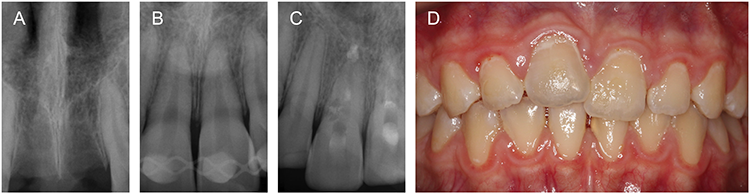

Die Folgen sind eine Pulpanekrose und ein erhöhtes Risiko einer bakteriellen Kontamination des Wurzelkanals [45,46], weshalb innerhalb 1 Woche eine Wurzelkanalbehandlung eingeleitet werden sollte (Abb. 3). Bei wurzelunreifen Zähnen ist hingegen eine Revaskularisation möglich. Diese erfolgt über einen Zeitraum von mehreren Monaten, in denen regelmäßige Kontrolltermine stattfinden sollten, um Anzeichen einer Nekrose frühzeitig zu erkennen [4,41,44,46].

Prof. Dr. Widbiller